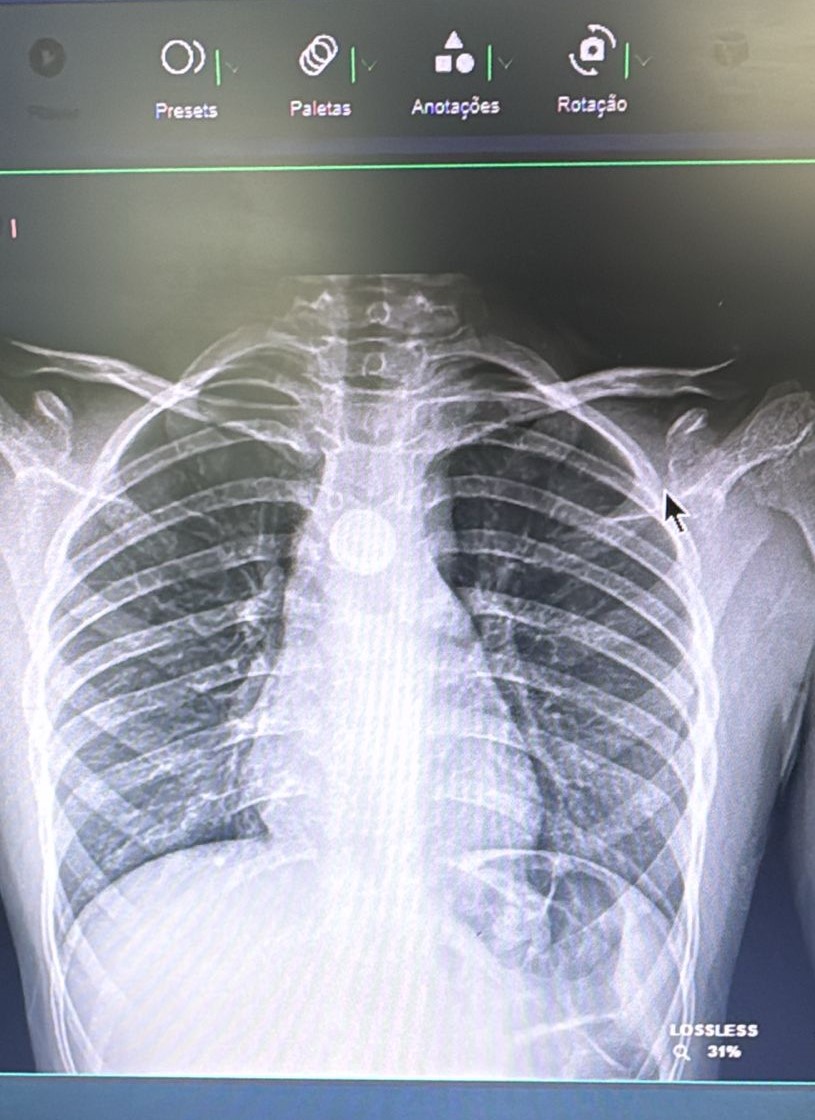

“O grande risco é quando o corpo estranho fica alojado no esôfago, local com mais sintomas e risco”, explica Giovana Tuccille Comes Brambilla, cirurgiã pediátrica do HCFMB. Segundo a especialista, o raio-x simples é o exame capaz de identificar a presença de um corpo estranho.